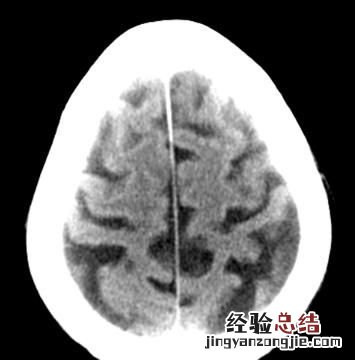

对于脑萎缩患者都有哪些症状,其中弥漫性大脑皮层萎缩以痴呆、智能减退、记忆障碍、性格改变、行为障碍为主 。有的伴有偏瘫和癫痫发作 。局灶性脑萎缩以性格改变为主;小脑萎缩以语言障碍及形体的共济失调和震颤为主 。